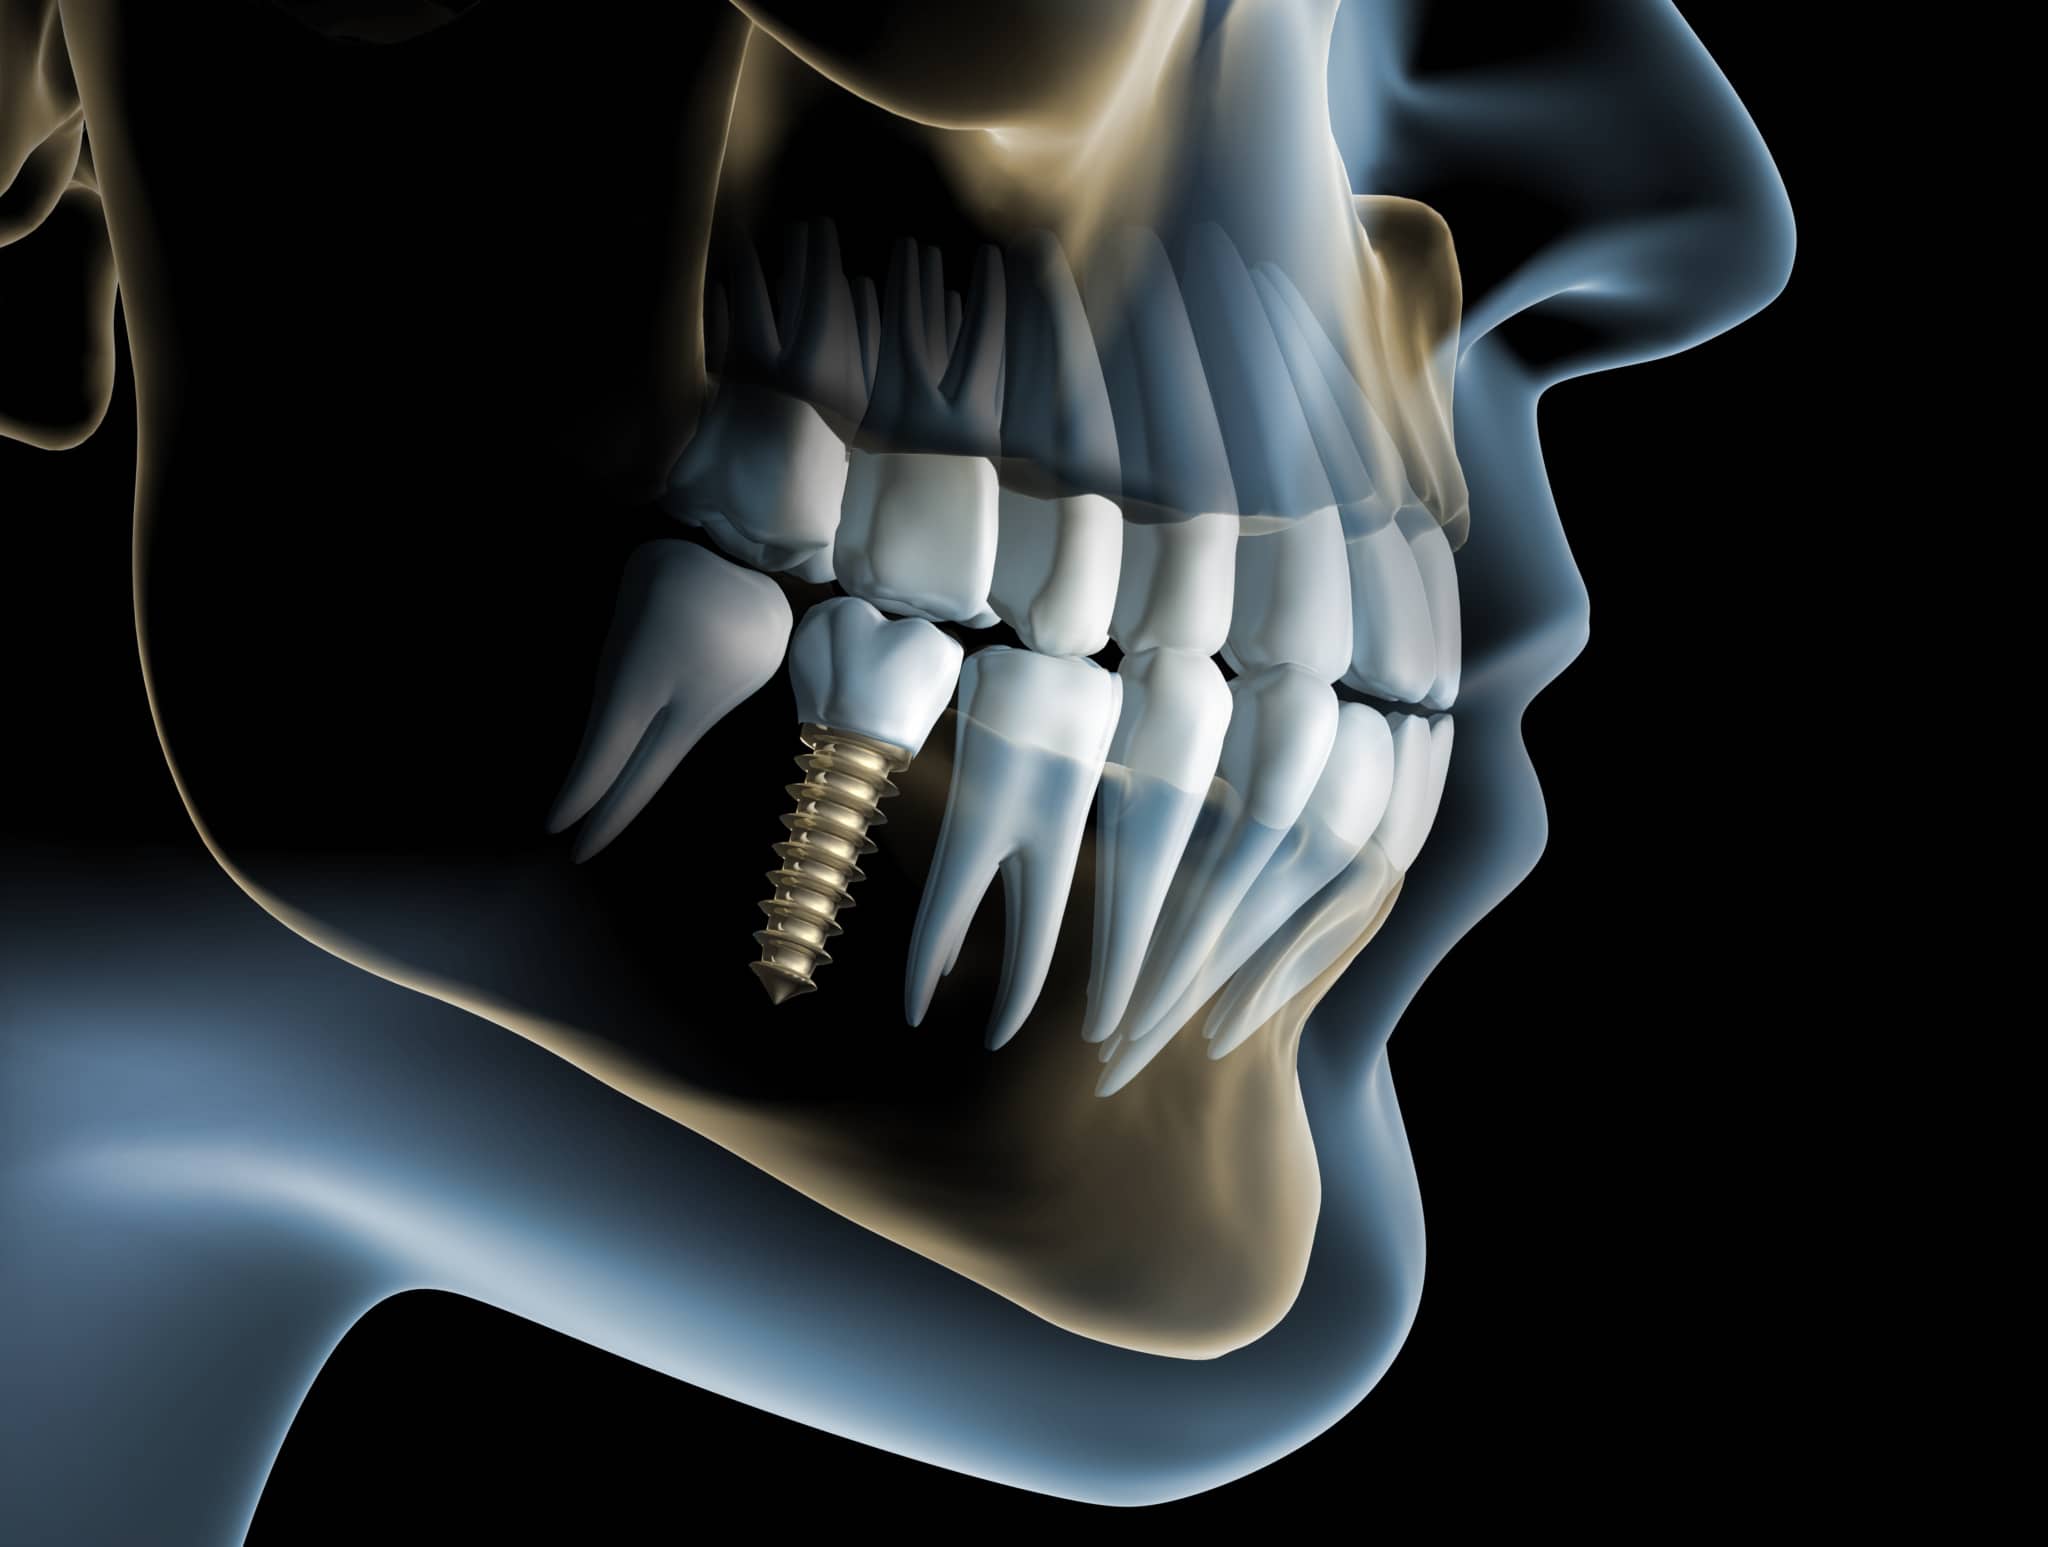

All-on-four Zahnbrücke - Malo Konzept - Schema

All-on-four: Brücke auf vier Zahnimplantaten

All on four mit einer verschraubten Brücke (Malo-Konzept)

Können Zahnimplantate in ausreichender Länge/Größe in den Kiefer implantiert werden, besteht die Möglichkeit, die vier Implantate mit einer festsitzenden Brücke zu verschrauben.

Das Behandlung mit Camfour™ sieht 4-6 Implantate je Zahnbogen vor. Meist reichen jedoch 4 Implantate aus. Die speziell für diesen Zweck ausgelegten Zahnimplantate werden mit einem Winkel von bis zu 45° in den Knochen eingebracht. Durch die geneigten Implantate ist der Spezialist für Implantologie unabhängiger vom noch vorhandenen Knochenvolumen und kann ohne einen vorherigen Knochenaufbau implantieren. Wichtig ist, dass die Zahnimplantate bereit unmittelbar nach Einsetzen stabil im Kieferknochen sitzen. Dies wird durch das spezielle All-on-4 ® / All-on-6 ®- Implantationsverfahren sichergestellt. Eine hohe „Primärstabilität“ der Implantate ist die wichtigste Grundvoraussetzung für eine Sofortversorgung mit Zahnersatz noch am gleichen Tag.